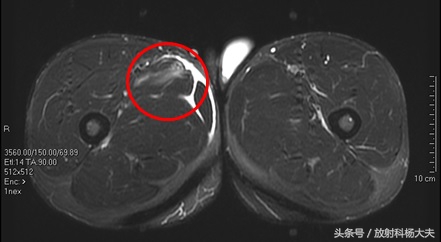

肌肉拉伤

肌肉拉伤可能是足球场上最多见的损伤了,为啥有的拉伤冷敷,休息就能好,而有的拉伤得做手术,甚至有可能导致职业生涯终止?其实答案都在MRI上,用MRI看肌肉有无拉伤,拉伤的程度如何,是目前最好的选择。

在MRI上,少于5%肌肉纤维的断裂,为I级损伤,大于5%,但没完全断裂的为II级损伤;完全断裂则为III级。比较多见的是I级损伤,MRI上可以看到肌肉的轮廓存在,但能看到白白的一片,代表水肿。